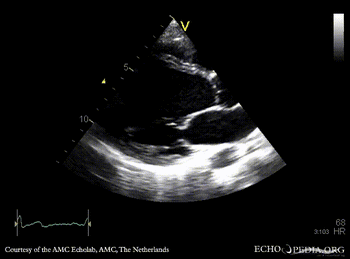

PLAX: Color Doppler, moderate mitral regurgitation A4CH: dilated poor left ventricle